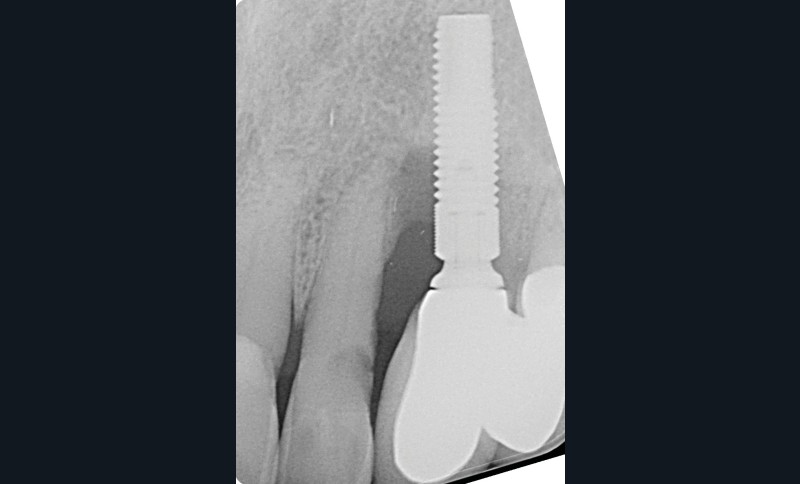

Le patient

- 70 ans

- Pas d’antécédents médicaux

- Ne fume pas

- Hygiène correcte

L’implant

- Site 23

- Mis en place il y a 12 ans